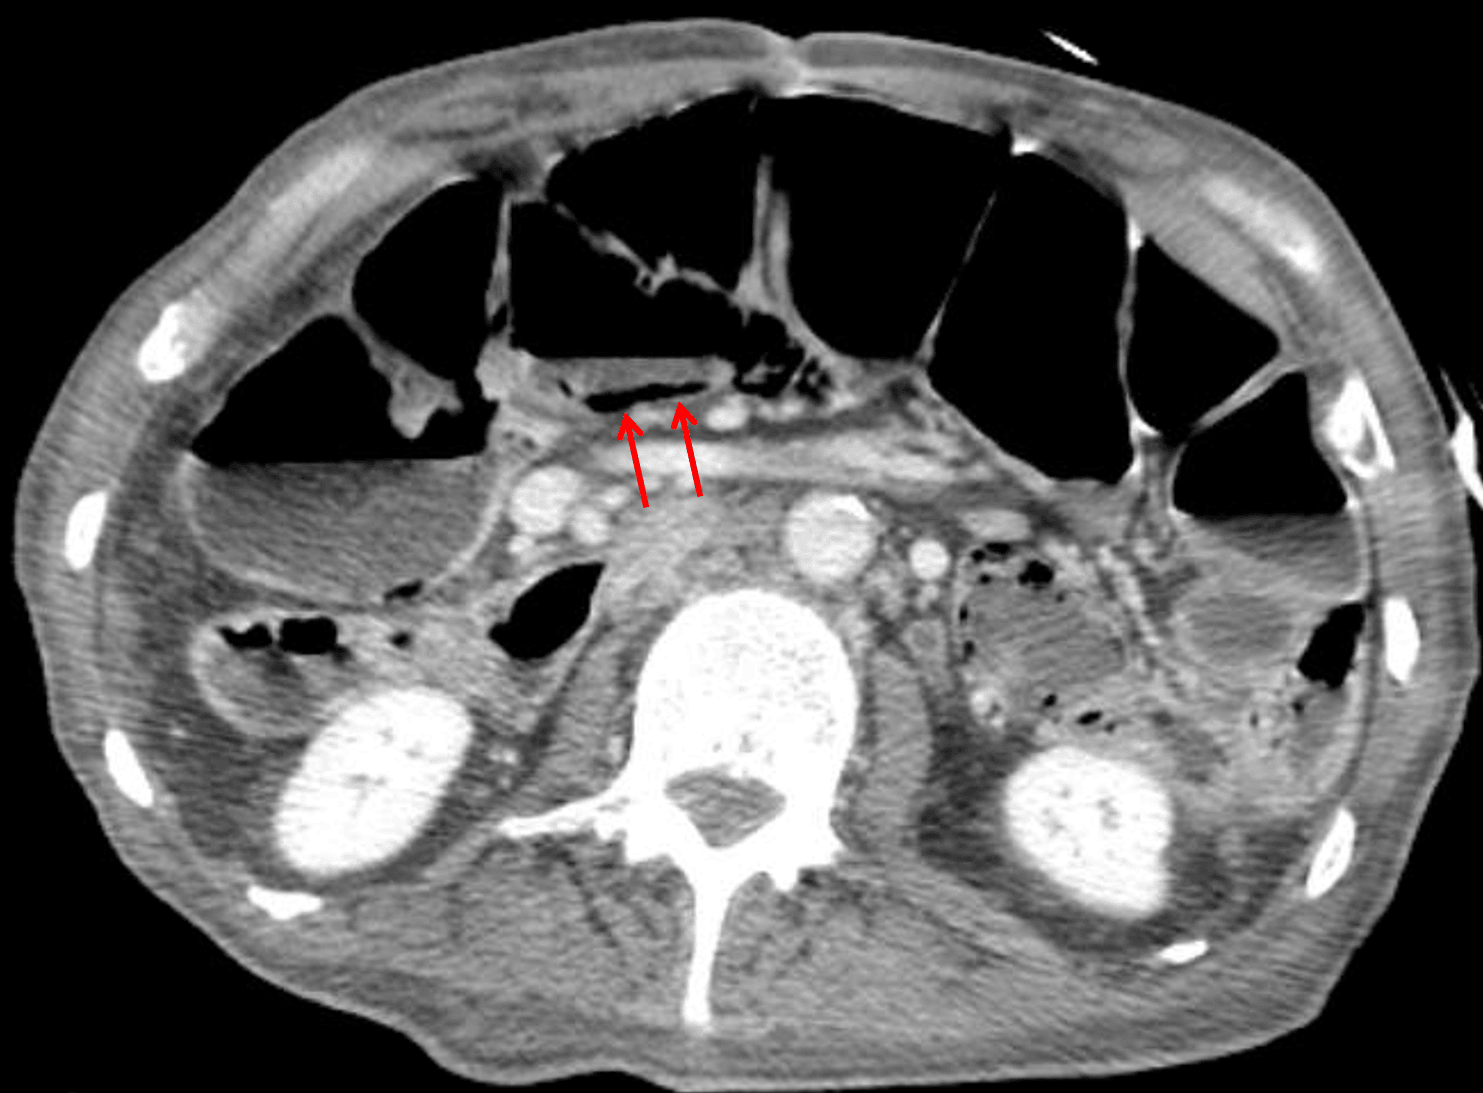

- In this case, the CT confirmed pneumatosis of the proximal transverse colon, but did not show portal venous gas or other signs of ischemia. After workup, the patient was thought to have a non-ischemic cause for pneumatosis

Pneumatosis of the proximal transverse colon confirmed on the subsequent CT (red arrows).